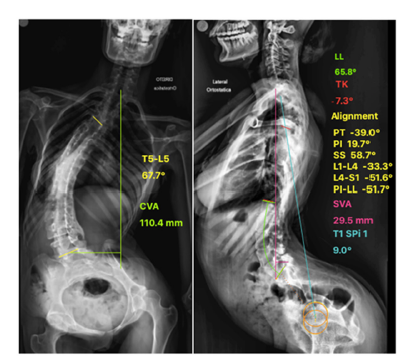

Using a full-length standing spine radiograph, preoperative spinopelvic alignment measurements were performed with Surgimap® software. The measurements were: anterior deviation of the sagittal vertical axis (SVA: +29.5mm); a negative pelvic tilt (PT: -39°), as the femoral heads were posterior to the midpoint of the sacral dome; increased lumbar lordosis (LL: -65.8°); pelvic incidence (PI: +19.7°) and the thoracic spine was in lordosis (CT -7.3°) (Figure 2).

Figure 2:a) Preoperative anteroposterior full-length standing spine radiograph shows significant posterior fusion bone mass and parameters of coronal alignment b) Lateral radiograph with the parameters of sagittal alignment. Note the anterior deviation of the sagittal vertical axis and the negative pelvic tilt, as the femoral heads are posterior to the midpoint of the sacral dome.